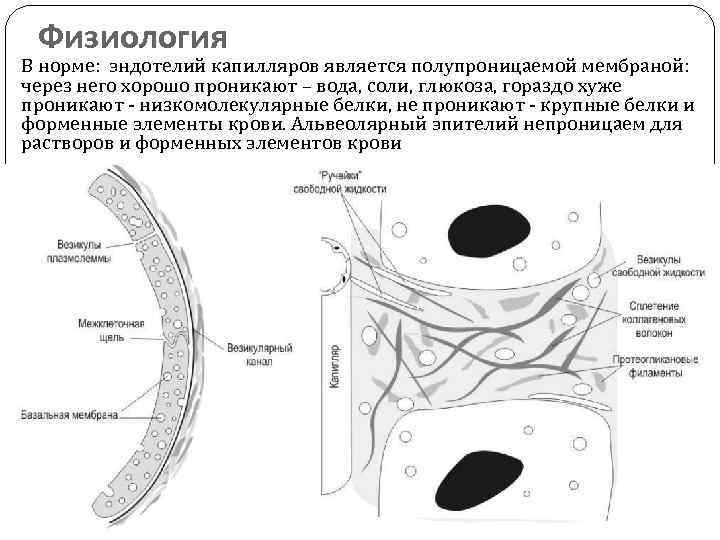

Физиология В норме: эндотелий капилляров является полупроницаемой мембраной: через него хорошо проникают – вода, соли, глюкоза, гораздо хуже проникают - низкомолекулярные белки, не проникают - крупные белки и форменные элементы крови. Альвеолярный эпителий непроницаем для растворов и форменных элементов крови

Физиология В норме: эндотелий капилляров является полупроницаемой мембраной: через него хорошо проникают – вода, соли, глюкоза, гораздо хуже проникают - низкомолекулярные белки, не проникают - крупные белки и форменные элементы крови. Альвеолярный эпителий непроницаем для растворов и форменных элементов крови